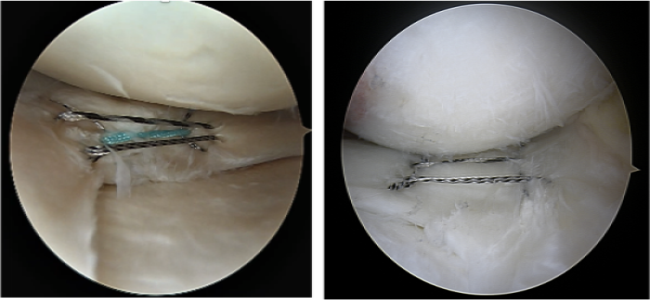

手術:内側ハムストリング腱と呼ばれる膝後内側の腱を束ねたものか、または膝前方の膝蓋腱とよばれる腱の一部を用います。関節鏡にて関節内を観察しながら、正確な位置にドリル孔を穿ち、ネジやボタンにて上記の腱に適切な張力をかけ固定します。手術による傷は、膝の周辺に3ー6cm程度ですが、半月板縫合術にはさらに数cmの追加皮膚切開が必要となります。また、関節鏡の刺入などのため、1cm程度の傷が数カ所必要となります。

前十字靭帯損傷のほぼ半数に認められる半月板損傷に対して可能な限り温存修復術を同時に行います。

手術:以前は、損傷した半月を切除することが主な治療法とされていましたが、半月切除後に長期間経過観察すると関節軟骨が傷むことから、現在では温存を目的とした治療が重要視されています。 私たちは、可能な限り半月の温存を図っています。ただし、半月の変性が強く、縫合しても治癒が期待できないと判断した場合には損傷した半月を部分的に切除します。

手術には関節鏡と呼ばれる内視鏡を用います。関節鏡手術では膝の前面2-3箇所に1cm程度の切開をいれ、そこからカメラや器具を挿入して、関節内の処置を行います。半月を縫合する場合には、膝の側面に約3cm程度の切開が必要になります。